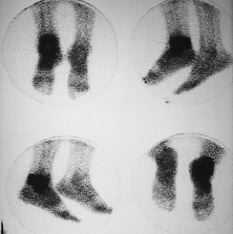

Fig. 3.--Gammagrafía ósea de ambos tobillos. Se observa hiperactividad en el tobillo derecho. Caso clínico núm. 2.

Fig. 3.--Radionuclide bone scan of both ankles. The right ankle shows increased activity. Clinical case 2.

Fig. 4.--Gammagrafía con galio de ambos tobillos. Muestra un depósito patológico que afecta, sobre todo, a estructuras posteriores del tobillo derecho. Caso clínico núm. 2.

Fig. 4.--Gallium radionuclide bone scan of both ankles. A pathological deposit affecting the posterior structures of the right ankle is visible. Clinical case 2.

A los 20 días de la implantación de la prótesis, comienza con un cuadro de fiebre, dolor y supuración en tobillo. Se realiza una gammagrafía ósea en la que se observa una hiperactividad en tobillo derecho sospechosa de complicación séptica. La gammagrafía con galio muestra un depósito patológico del mismo que afecta a estructuras posteriores de la articulación y que resulta compatible con infección.